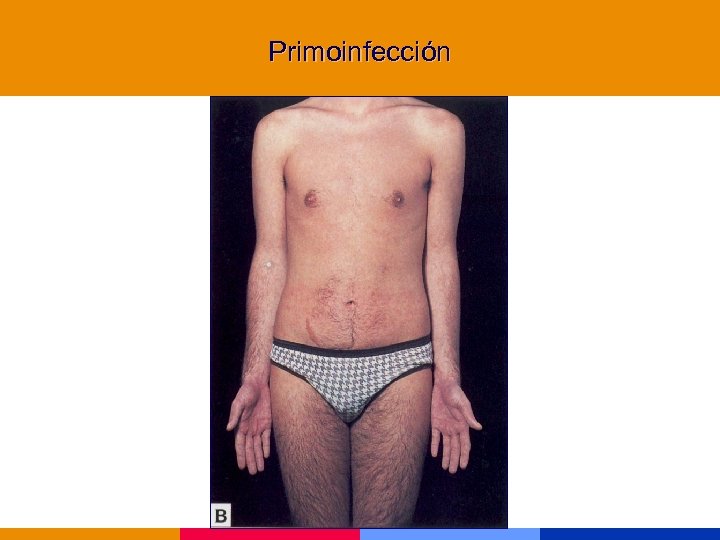

Primoinfección

Primoinfección

Primoinfección

Primoinfección

Primoinfección

Primoinfección

Primoinfección

Primoinfección